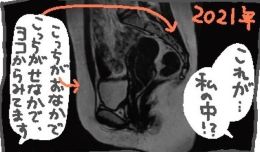

vol.281 「MRI」

作:ド謙遜